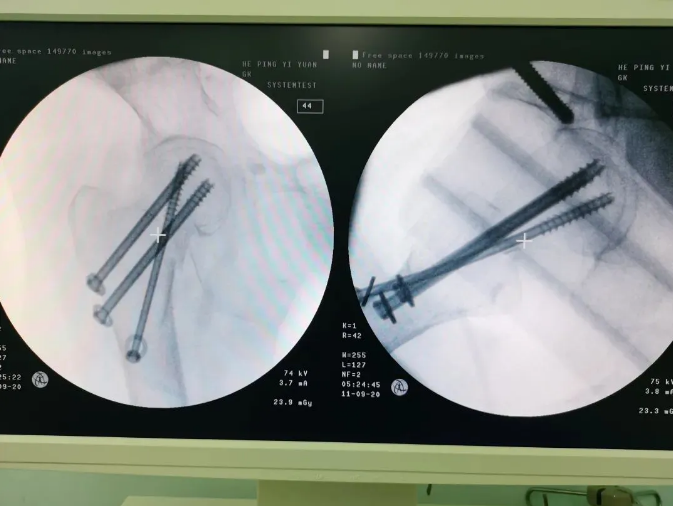

Ììçá»úеÈËÖÃÈëÂݶ¤

Âݶ¤ÖÃÈëºó

Ììçá?¹Ç¿ÆÊÖÊõ»úеÈ˵ļÓÈ룬£¬£¬£¬£¬£¬£¬Äܹ»ÐÖúÒ½ÉúΪÐèÒª¾ÙÐÐÊÖÊõµÄ»¼ÕßÌṩ¸üÇå¾²¡¢ÓÅÖÊ¡¢¸ßЧµÄÒ½ÁÆ·þÎñ£¬£¬£¬£¬£¬£¬£¬×ÊÖú»¼Õßɨ³ý²¡Ô£¬£¬£¬£¬£¬£¬ÊØ»¤»¼Õß¿µ½¡£¬£¬£¬£¬£¬£¬£¬Ìá¸ß»¼ÕßÉúÑÄÖÊÁ¿¡£¡£¡£¡£¡£¡£ÔÚÌìçá?¹Ç¿ÆÊÖÊõ»úеÈ˵ÄÐÖúÏ£¬£¬£¬£¬£¬£¬£¬ÊõÖл¼ÕßÇпڽöÈý¸öС¿×£¬£¬£¬£¬£¬£¬£¬³öѪÁ¿ÉÙ£»£»£»£»£»Êõºó³ÂÆÅÆÅ¾Ò»¶Îʱ¼äµÄ¿µ¸´ÑµÁ·±ã¿ÉÏ´²Ô˶¯£¬£¬£¬£¬£¬£¬£¬ÏÖÔÚÒÑ¿µ¸´³öÔº¡£¡£¡£¡£¡£¡£